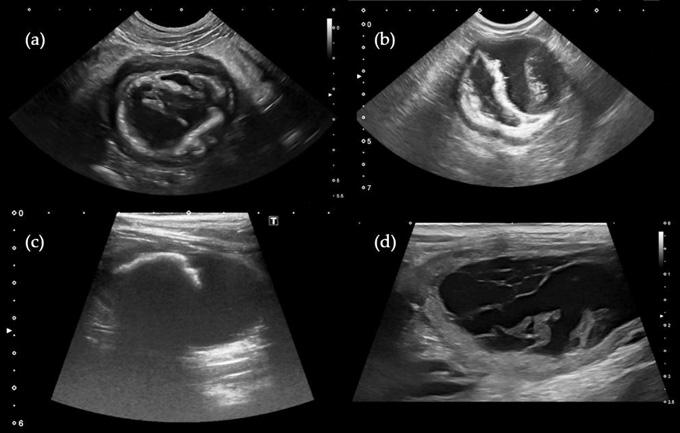

УЗИ мочевого пузыря у кошек

УЗИ мочевого пузыря — безопасный и высокоинформативный метод диагностики, позволяющий получить достоверную информацию о строении органа, его структуре и расположении. Позволяет выявить врожденные и приобретенные патологии, инфекционные и воспалительные процессы на начальных стадиях. Процедура не травматичная, проходит без боли и дискомфорта для животного.

УЗИ мочевого пузыря у кошки позволяет определить расположение внутреннего органа, его форму и размер, структуру. Также высокоинформативная процедура позволяет оценить кровоснабжение, выявить доброкачественные и злокачественные опухоли на начальной стадии.

Животное находится в положении лежа. Врач наносит на исследуемую область специальный гель, настраивает датчик и начинает водить его по месту расположения мочевого пузыря. На мониторе появляется увеличенное изображение внутреннего органа, по которому можно определить его размеры и структуру, выявить новообразования, воспалительные процессы.